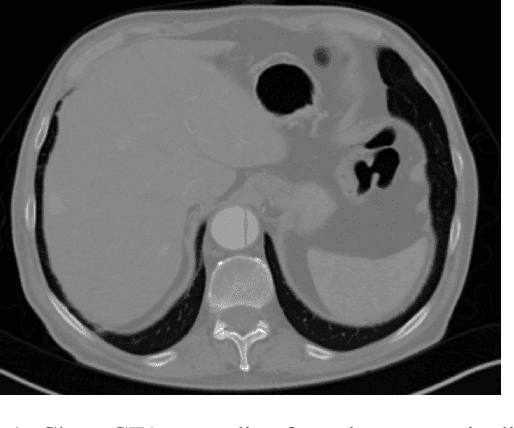

Abstract:Medical imaging is an important tool for the diagnosis and the evaluation of an aortic dissection (AD); a serious condition of the aorta, which could lead to a life-threatening aortic rupture. AD patients need life-long medical monitoring of the aortic enlargement and of the disease progression, subsequent to the diagnosis of the aortic dissection. Since there is a lack of 'healthy-dissected' image pairs from medical studies, the application of inpainting techniques offers an alternative source for generating them by doing a virtual regression from dissected aortae to healthy aortae; an indirect way to study the origin of the disease. The proposed inpainting tool combines a neural network, which was trained on the task of inpainting aortic dissections, with an easy-to-use user interface. To achieve this goal, the inpainting tool has been integrated within the 3D medical image viewer of StudierFenster (www.studierfenster.at). By designing the tool as a web application, we simplify the usage of the neural network and reduce the initial learning curve.